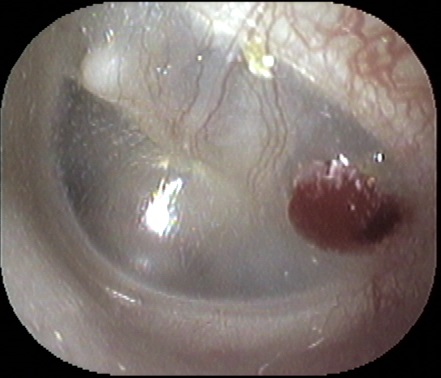

子供さんが夜間に突然耳を激しく痛がって泣いて困った経験はありませんか?

起こる時間帯は決まって夜中なのです。「中耳炎かも?」とあわてて病院を探し救急病院

を受診という方は多いと思われます。

↑は鼓膜表面に水泡が出来ている状態で、非常に激しい痛み

を伴いますが